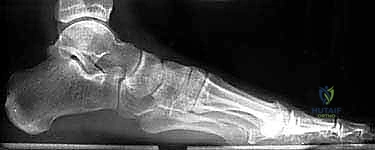

- الأشعة السينية (X-rays) متعددة الزوايا: لتقييم الانهيار العظمي وزوايا الكعب (مثل زاوية بوهلر وزاوية جيسان).

- الأشعة المقطعية ثلاثية الأبعاد (3D CT Scan): وهي الخطوة الذهبية والأهم في عيادة الدكتور هطيف. تتيح هذه الأشعة بناء نموذج ثلاثي الأبعاد دقيق للكعب المشوه، مما يسمح بتحديد أماكن الانحشار العظمي بدقة المليمتر، ومعرفة مدى تلف الأسطح المفصلية. بناءً على هذه الصور، يتم وضع خطة "القطع العظمي التصحيحي" قبل دخول غرفة العمليات.